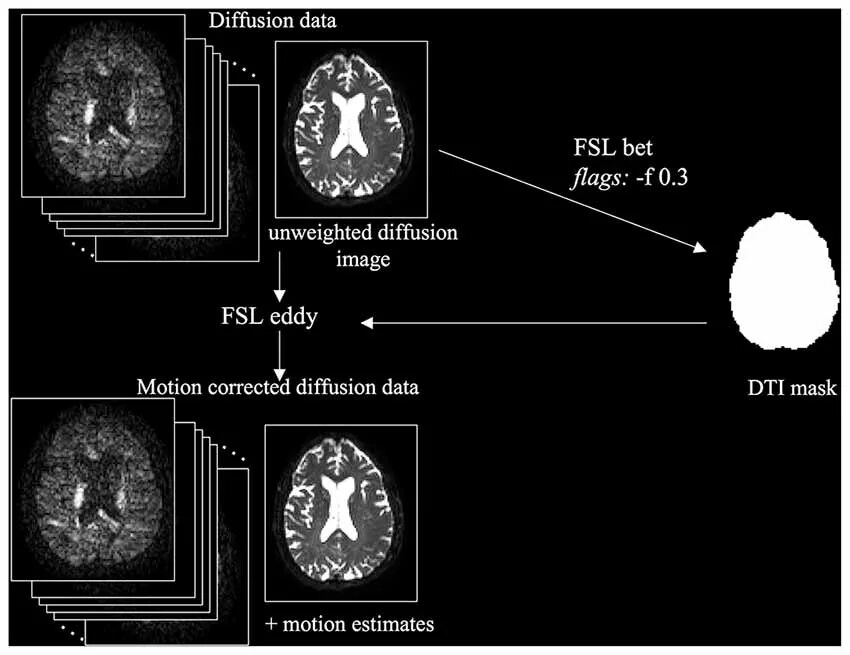

Diffusion tensor